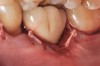

The following case report provides an example of this case scenario: A 24-year-old white male presented with congenitally missing tooth No. 26 restored with a single-tooth cement-retained implant restoration. The implant was placed excessively to the facial aspect of the edentulous site and too shallow, and the periodontal phenotype was thin scalloped (Figure 32). In an effort to mimic the lost midfacial soft tissues, pink ceramics were used as a cosmetic facade. Even though the restoration was not in the esthetic zone, the patient was highly displeased with the esthetic outcome and sought remediation.

The crown and screw-retained custom abutment were removed, and a surgical cover screw was placed into the implant, thereby allowing spontaneous gingival augmentation in situ (Figure 33 and Figure 34). Note that the lingual aspect of the implant site was significantly more coronal than the labial aspect, which was positive because the defect would be limited to a facial–lingual defect. A fixed RBR bridge was cemented on the adjacent teeth and used as a tooth-supported transitional provisional restoration (Figure 35). A few weeks were allotted to let the soft tissue heal and migrate around the cover screw (Figure 36) to see if there would be complete coverage, thereby allowing a soft-tissue augmentation procedure to be performed with primary flap closure as in clinical scenario No. 2. The major obstacle in achieving a positive tissue response was that the implant depth was also deficient because the implant–abutment connection was at the level of the free gingival margin. It was decided that the best treatment option would be to remove the implant. A high-powered reverse-torque device (Fixture Remover Kit, NeoBiotech, www.neobiotechus.com) was used to remove the implant atraumatically (Figure 38 through Figure 41). The implant socket was allowed to heal for several months not unlike an extracted tooth (Figure 42). A new implant was placed in a better position from both a restorative and esthetic perspective (Figure 43), and after a few months of healing, a new crown was made (Figure 44). A satisfactory functional and esthetic result was achieved (Figure 45 and Figure 46) without employing pink porcelain.

Fig 35. A transitional resin-bonded-retained (RBR) bridge that was tooth supported was placed to allow soft-tissue maturation.

Figure 35

Fig 36. Two weeks after RBR placement, the soft tissue did not adequately cover the implant. The problem was in poor implant angulation and proper depth to allow the soft tissues to cover over.

Figure 36